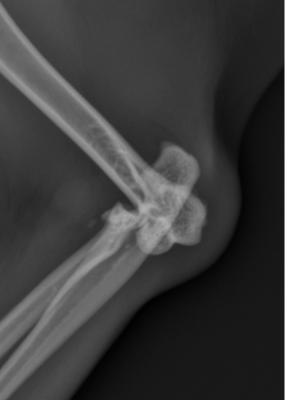

Le diagnostic repose sur des radiographies ciblées :

- Face : met en évidence le décalage latéral du radius et de l’ulna

- Profil : évalue la hauteur du déplacement et détecte d’éventuelles fractures

- Vues obliques : parfois nécessaires pour identifier une luxation latérale isolée

Ces examens servent aussi à planifier le traitement, conservateur ou chirurgical.